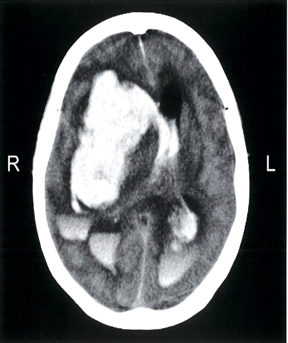

Noncontrast CT of the head (axial section)

- The large hyperdensity in the region of the right basal ganglion indicates a massive intracerebral hemorrhage that has caused a midline shift to the contralateral side. There are focal areas of cerebral edema (hypointense (black) areas) in the perihemorrhagic area. The hemorrhage has extended into the lateral ventricles ,

- Blood, being denser than CSF, has settled in the posterior horns of the lateral ventricles as these areas are dependent fluid-filled portions in the supine position.